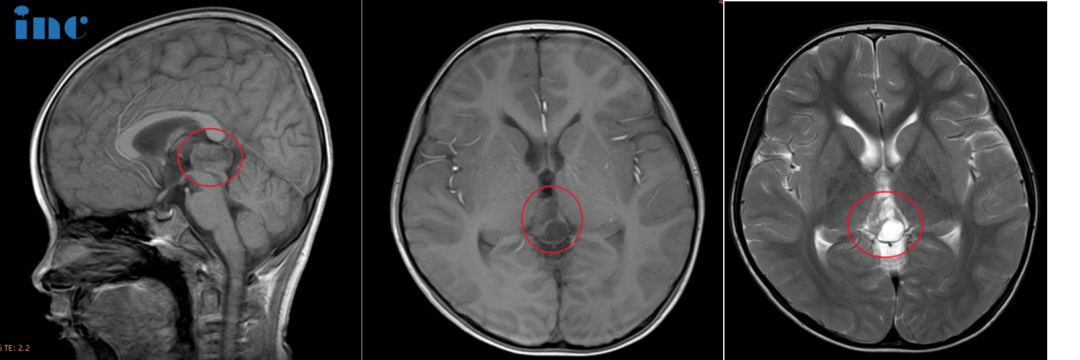

6岁男孩-松果体占位性病变

病史摘要:6岁的鑫鑫,2021年由于意外摔破头皮就诊,CT检查后居然发现松果体区阴影和部分钙化灶,进一步进行MRI见检查后,发现22*14*17mm病灶。鑫鑫父母回想此前孩子确实有身高发育缓慢,腿部量不足以及偶尔走路不稳易绊倒等情况。检查出病灶后鑫鑫进行定期复查,鑫鑫激素检查水平正常,期间病灶有变化。2023年7月MRI结果提示病灶大小:25*19*15mm。国内医生建议尽量手术切除,由于两年期间形态变化不大,也可以继续保守治疗。但是患儿的状态并不太好,睡眠不稳、逻辑理解能力较差、记忆力也出现问题以及系列心理上的问题……

手术过程:北京时间10月31日,巴教授中国疑难示范手术期间,在首都医科大学附属北京天坛医院巴教授顺利为鑫鑫成功顺利全切手术,术后功能无影像。ICU外,巴教授为当天接受示范手术的鑫鑫父母交流孩子的状态。教授开心地说道:“Leg lay is okay,and everything is good.(腿没有问题,孩子状况很好)。”天坛医院的神经外科医生也激动,为鑫鑫点赞:小伙子棒。

术后情况:手术后1天转出ICU转入普通病房,父母告诉巴教授孩子很好,现在能吃饭、能说话、身上也不疼痛。鑫鑫还能捏住巴教授的大手,四肢活动正常,一旁的父母高兴。术后2天查房,鑫鑫用英语说出自己较喜欢的玩具坦克:“Tank!”,身边的爸爸妈妈都笑开了花。